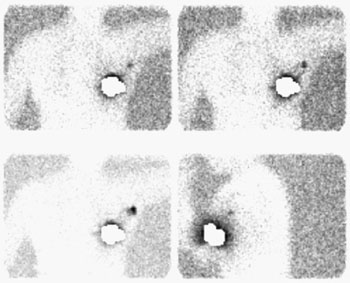

The frontal chest radiograph below was performed on a patient who presented to the emergency department following a 30 foot fall. The radiograph demonstrates widening of the mediastinum and an aortic contour abnormality with loss of the sharp outline of the aortic knob. Many of the other findings of aortic injury were not present and a CT of the chest was performed to evaluate for the presence of aortic injury ( Click here to view the CT scan and arteriogram).